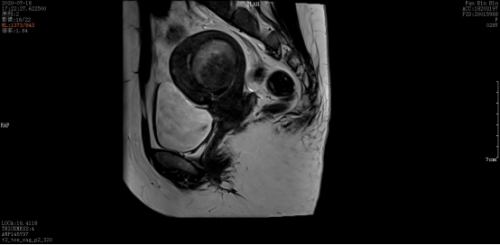

术前:

微波消融后肌瘤病灶内会发生凝固性坏死,即刻超声造影就可以看到病灶内没有造影剂充填。磁共振增强扫描病灶内呈现充盈缺损,增强后呈黑色区域,表示病灶坏死区域。坏死的病灶随时间推移,会逐渐萎缩吸收,子宫体积也会有一定的缩小,从而使痛经、月经量多等临床症状得到缓解和改善。